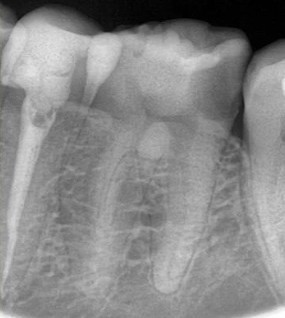

Кхалил Абаноуб Адли Абдуллах: портфолио (4)